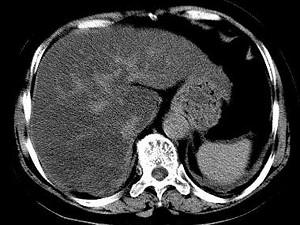

问题 男,32岁,肥胖,常酗酒,肝肋下一横指,肝区轻微压痛,影像表现如图,应诊断为 ( )

选项 A、肝豆状核变性 B、肝含铁血黄素沉着 C、肝硬化 D、脂肪肝 E、肝炎

答案 D